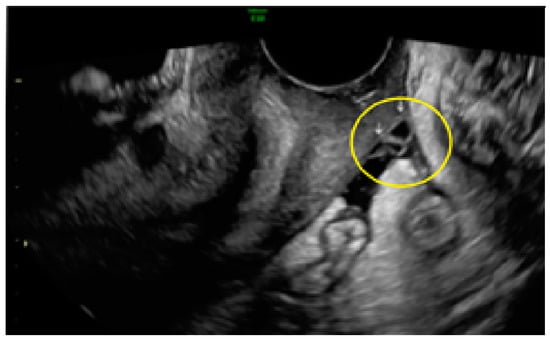

3.1. Cystic Solitary Lesion

3.2. Cystic Multiple Separate Lesions